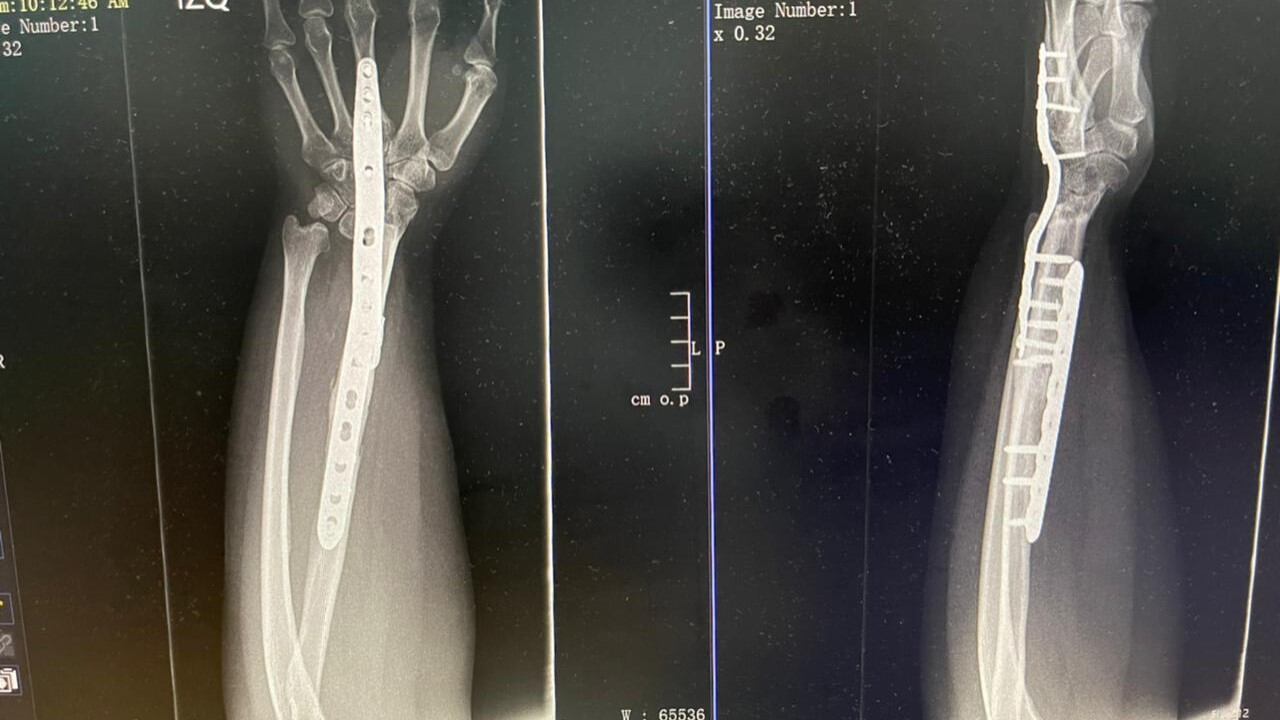

Ante la posibilidad de que creciera e invadiera otros huesos, los médicos decidieron remover el tumor, con el problema de que quedaría un vacío en el antebrazo, pues no tenía hueso que lo soportara en su totalidad. Ese vacío fue cercano a los 10 centímetros, proporciones que impedirían el funcionamiento de la muñeca. El radio es vital porque el cuerpo lo utiliza para mover las articulaciones de codo y muñeca. En el intento de evitar una amputación se pidió apoyo a Josías Juantá, especialista en Microcirugía del Hospital San Juan de Dios.

Fue así como se optó por reconstruir la mano utilizando el peroné, uno de los huesos de la pierna. La cirugía se hizo de forma que permitiera movilidad y funcionalidad a la muñeca pero sin causar daños en la pierna que afectaran su estabilidad y sus habilidades.

De esta forma, el procedimiento fue extirpar el tumor y luego extraer las partes del cuerpo requeridas para la reconstrucción. Estos tejidos se ponen en un molde y se les da forma; después se colocan donde estaba el tumor y se “unen” los vasos sanguíneos con microcirugía. Debe hacerse de forma muy detallada y con instrumental especial mínimo para que el flujo de la sangre se mantenga constante. La resección del tumor demoró dos horas. La reconstrucción, al ser un proceso más detallado, tomó cinco horas.

Esta es la primera cirugía en Costa Rica en la que el hueso y el tejido del peroné se utilizaran para salvar una muñeca. La técnica se realizó en junio del 2018, cuando Sharon tenía 22 años. Los médicos aclararon que no se dio a conocer antes debido a que la alta complejidad de estos procedimientos requieren un seguimiento más riguroso y continuo en el tiempo, antes de ser declarados como exitosos.